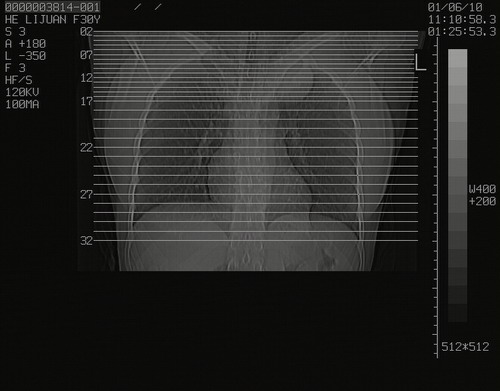

怀孕3个月时(2009-3至4月间),自述突感左侧前后胸疼痛1天,以前胸明显,随后偶感闷痛,余未见异

左肺尖脊柱旁沟肿块,境界清楚,边缘光滑,密度不均,内有多发点片状钙化,考虑良性肿瘤,骨软骨瘤或神经源性肿瘤可能,肺错构瘤不除外。

左后上纵隔见一类圆形肿块影,外侧边界清,密度不均匀,内可见点状钙化影,增强呈不均匀强化,考虑神经源性肿瘤可能。期待病理结果。